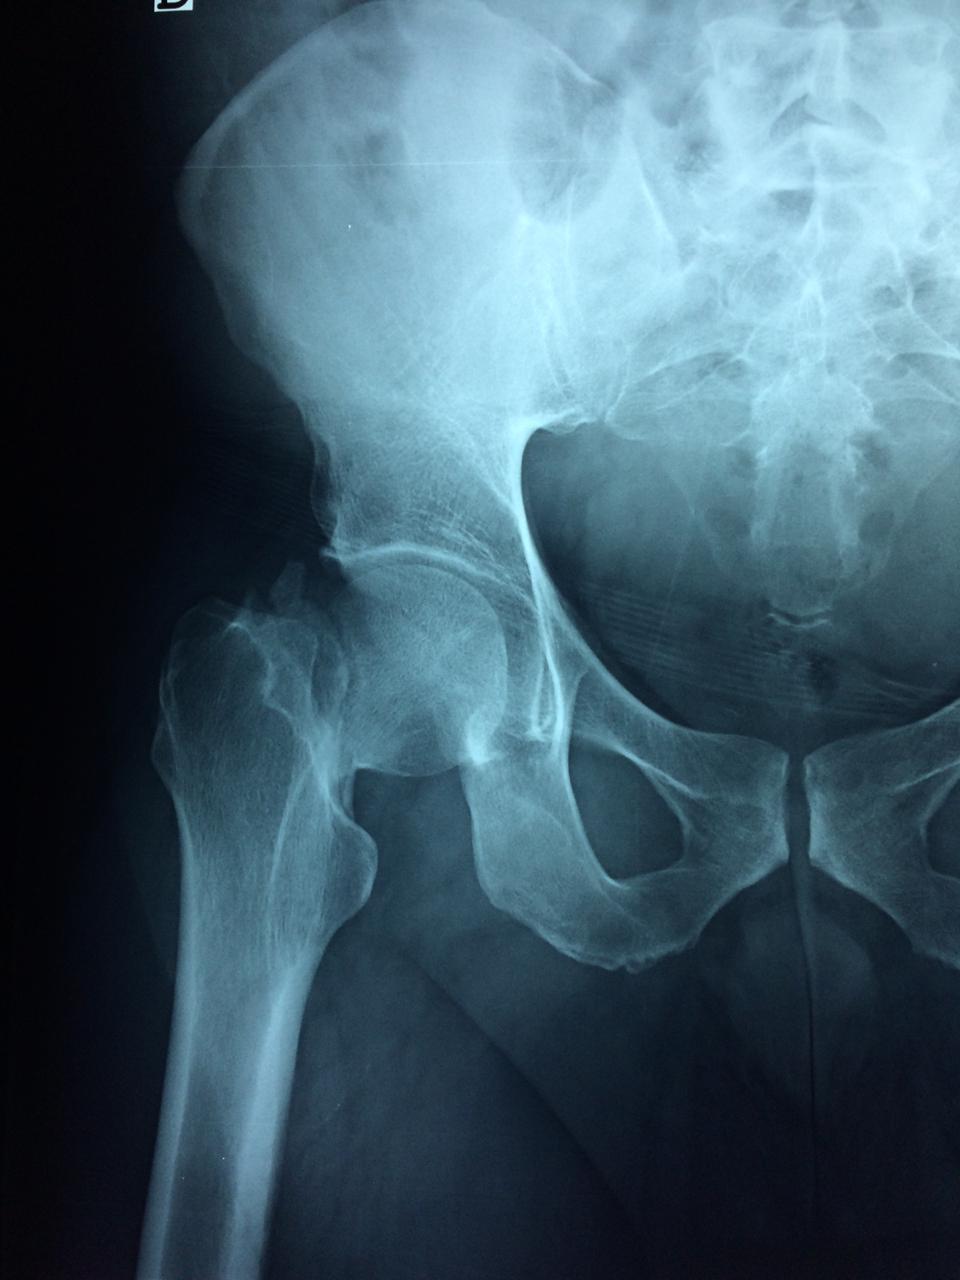

Cirugía de Fémur - Cadera

La cirugía de fractura de cadera se realiza para reparar una ruptura en la parte superior del hueso del muslo. Este hueso se denomina fémur.

Es parte de la articulación coxofemoral. Si una fractura de cadera no recibe tratamiento, es posible que deba permanecer en una silla o en la cama.